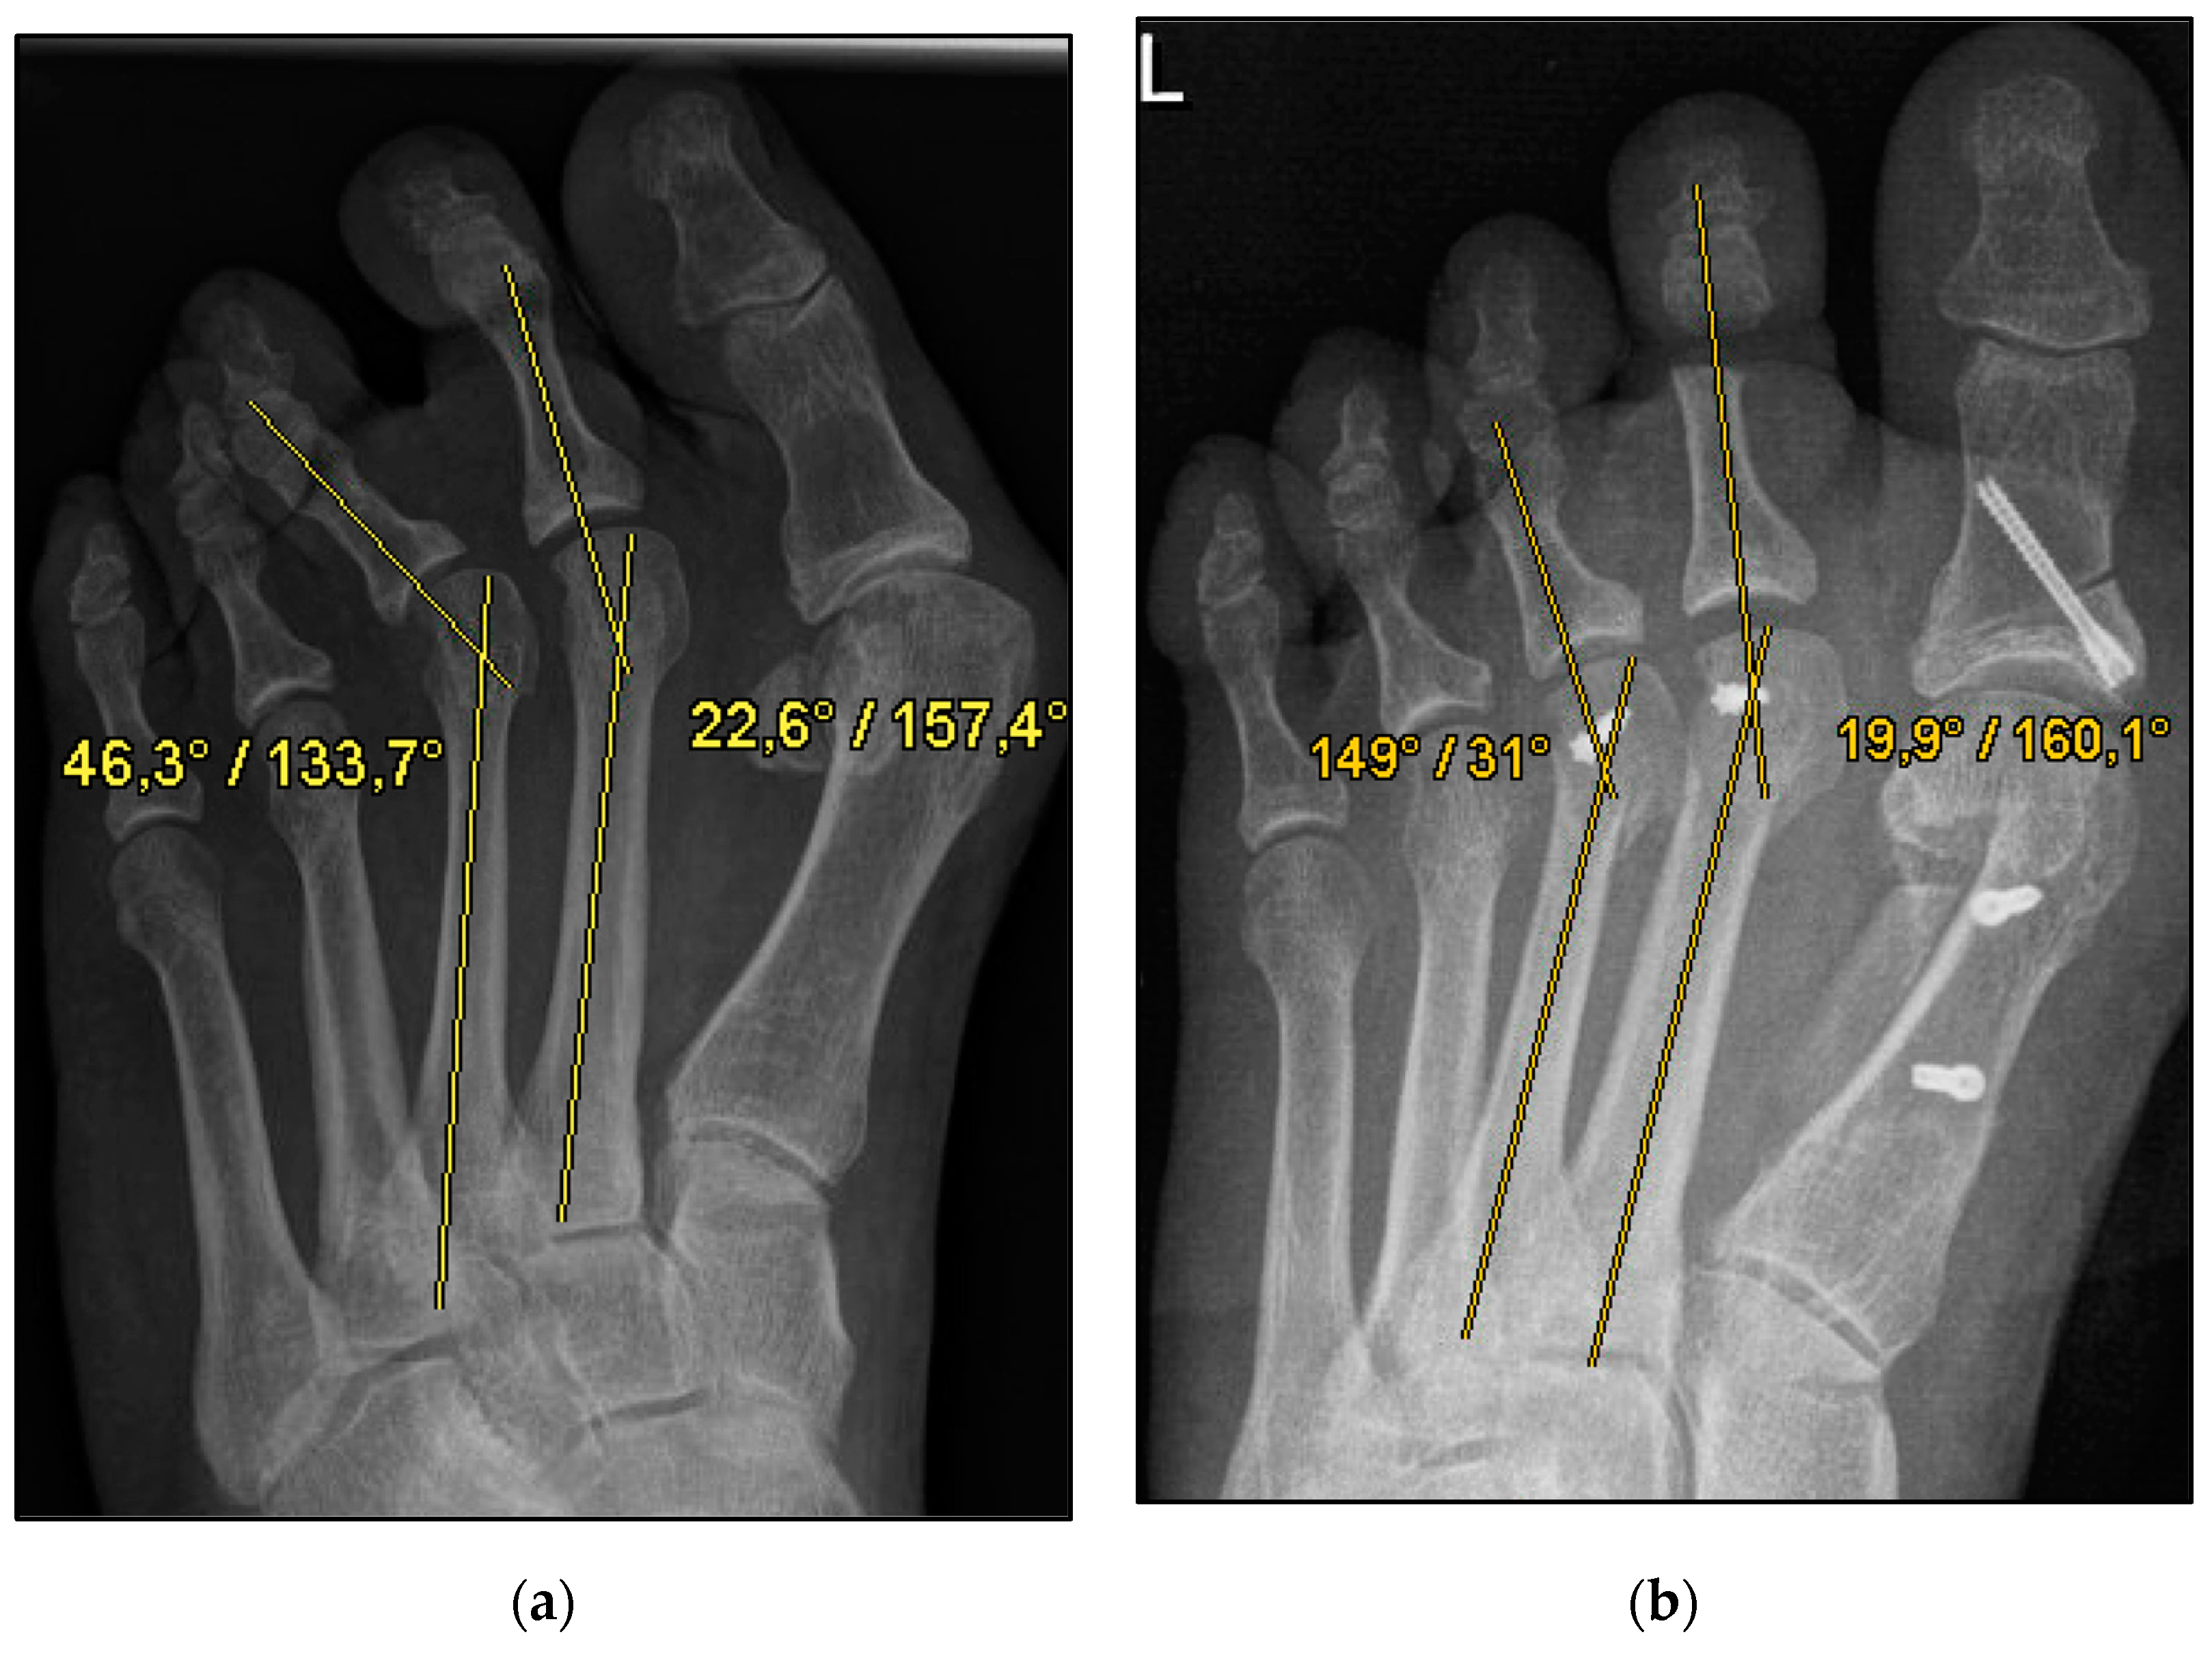

Figure 1.

Pre- and postoperative radiographic results of combined hallux valgus surgery and Weil osteotomy of metatarsal 2 and 3 (group A with screw), left foot. (a) Weight-bearing radiograph: anteroposterior view preoperative, (b) weight-bearing radiograph: anteroposterior view, 6 weeks postoperative.